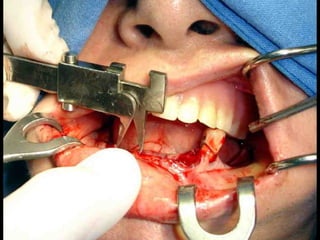

Plastia de maxilares para implantes dentales.

Plastia alveolar con factores de crecimiento y

traspalnate de hueso cadaverico

La conformación quirúrgica de un contorno alveolar adecuado es

determinante para la correcta aplicación y aceptación de los implantes

de titanio, aquí proponemos una técinica para lograr el espesor óseo

suficiente y la corrección estética del proceso, ya que antiguamente al

extraer un diente se acostumbraba presionar las tablas alveolares

“para cohibir la hemorragia”, con el colapso subsiguiente de la región.

Plastia de maxilarespara implantes dentales.

Plastia alveolar confactores de crecimiento y traspalnate de hueso cadaverico

La conformación quirúrgicade un contorno alveolar adecuado es determinante para la correcta aplicación y aceptación de los implantes de titanio, aquí proponemos una técinica para lograr el espesor óseo suficiente y la corrección estética del proceso, ya que antiguamente al extraer un diente se acostumbraba presionar las tablas alveolares “para cohibir la hemorragia”, con el colapso subsiguiente de la región.